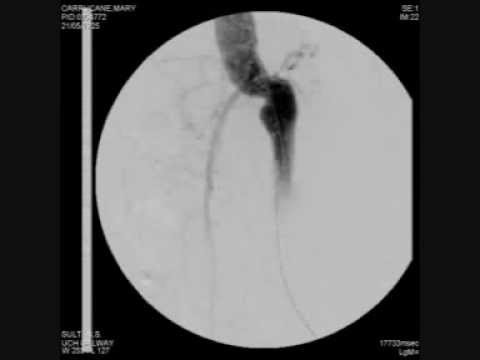

Hellow guys, Welcome to my website, and you are watching Prof Sherif Sultan Consultant Vascular Surgeon Galway Cinic. and this vIdeo is uploaded by Galway Clinic at 2017-07-29T05:39:07-07:00. We are pramote this video only for entertainment and educational perpose only. So, I hop you like our website.